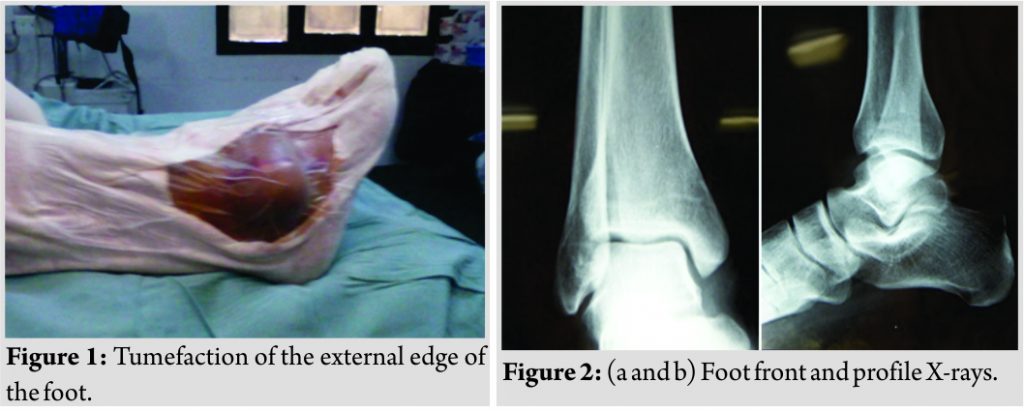

Patient G.J, 60 years old with no particular pathological history, was hospitalized for exploration of a swelling of the external border of her right foot that had been evolving for 2 years. The physical examination showed an oval swelling of 3 cm long, lying in the submalleolar external region, painless, mobile, and of firm consistency (Fig. 1). The biological assessment did not show any inflammatory syndrome. Standard radiography was normal (Fig. 2).